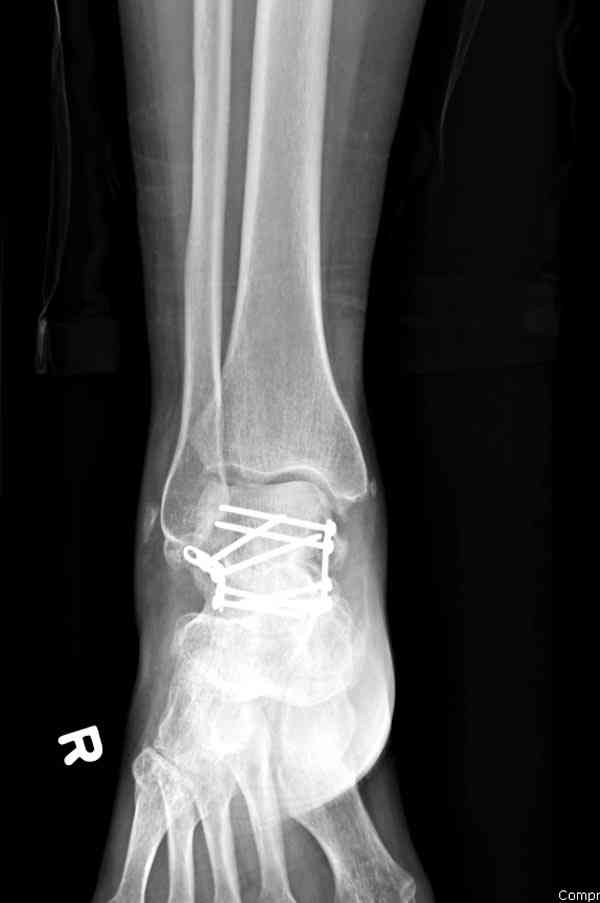

Случай с множественным оскольчатым переломом тарана оперированный из двойного доступа.

Через 2 мес.:

Через 8 мес.:

Через 14 мес.: